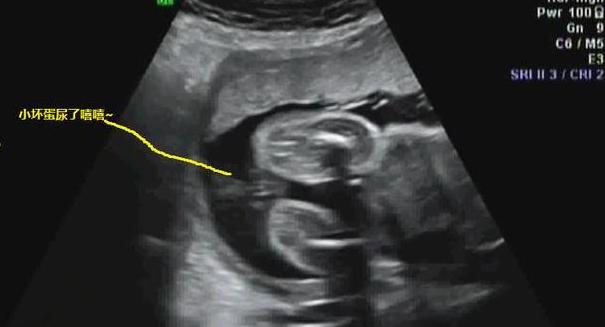

前些天,年轻孕妈夏岚按照约定,在23周的时候,在老公的陪同下来到医院,准备进行四维彩超检查。

检查过程中,屋内气氛十分严肃,仿佛地上掉一根针都可以清晰地听到。

就在这时,医生看着四维彩超的屏幕,突然笑了起来,而准奶爸看到画面后,也是羞红着脸笑骂:

“不害臊!”

医生笑着摆摆手,指着仪器说道:

“别担心,是你肚里的小家伙在撒尿。”

听到这话,夏岚也有些不好意思了,笑道:

“小家伙这么调皮,净干坏事!等你出来了,看我怎么收拾你!”